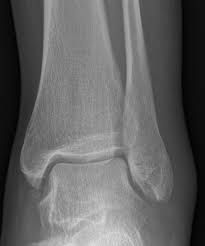

엑스레이상

인대가 늘어났다고

치료받으러 오시는 분들이

많습니다.

그런데

X-ray에서

인대가 늘어난게

잘 보일까요?

위 X-Ray 영상처럼

"인대" 그 자체는

잘 보이지 않고요.

"인대"란

뼈와 뼈 사이를 연결하는

구조물이기 때문에

뼈와 뼈 사이를 벌린 상태로

벌어지는 거리를 측정하여

인대의 상태를 진단합니다.

2개의 뼈를 연결하는

인대가 파열되면

두 뼈를 벌린 간격이

정상 범위를 넘어갑니다.

가장 많이 다치는

앞쪽 거비인대(ATFL)는

거골과 비골의 거리가

4-6mm 이상 벌어졌을때

완전파열을 의심할 수 있고요.